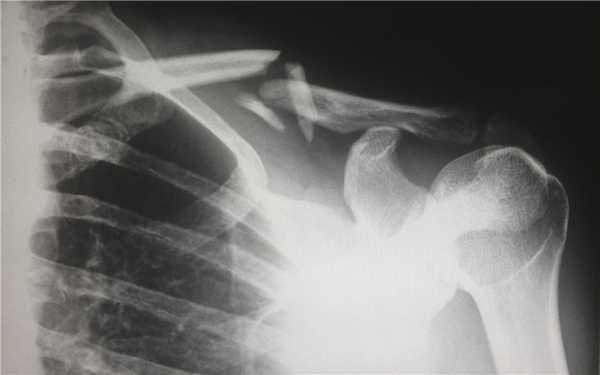

КТ при переломах

Компьютерная томография (КТ, или МСКТ) является наиболее информативным методом визуальной оценки посттравматических изменений костей, суставов и окружающих тканей. В отличие от других видов лучевой диагностики, при КТ тело человека сканируется поперечно тонкими срезами, на сканах визуализируются ткани различной морфологической структуры (кости, внутренние органы, системы кровообращения и лимфотока), а на основании полученных изображений создается трехмерная модель-реконструкция исследуемой части тела и сканы в трех плоскостях.

Таким образом, будучи пространственным, а не плоскостным (как рентген) методом визуализации любых костных анатомических структур, КТ позволяет достоверно определить тип травмы, увидеть возможные осложнения и повреждения соседних тканей. Поэтому среди врачей это исследование считается предпочтительным для диагностики переломов, особенно осложненных, в том числе внутрисуставных, не рутинных. Плюсом КТ также является оперативность и простота обследования для пациента.

Зачем делать КТ при переломе?

Компьютерная томография позволяет детально визуализировать кости, суставы и окружающие ткани в режиме 3D, что делает этот метод идеальным для диагностики переломов разной степени сложности. Врач-рентгенолог увидит даже небольшое смещение костей, сколы и трещины, а также сможет точно рассчитать любые отклонения с помощью программного обеспечения. На трехмерной реконструкции отсутствуют артефакты (искажения), так что врач сможет точно и достоверно описать результат в заключении.

На КТ в высоком разрешении будут видны деструктивные и воспалительные процессы в костях, суставах и, что не менее важно, в прилегающих тканях. Квалифицированный врач-травматолог, хирург или другой специалист сможет не только ознакомиться с письменным заключением, но и изучить КТ-сканы.

Когда делать КТ, а когда рентген при переломе?

Алгоритм диагностики переломов обычно таков, что сначала пациента осматривает врач-травматолог, после отправляет пострадавшего на рентген. Исключением являются заведомо диагностически сложные случаи, когда предпочтение сразу отдается КТ — переломы черепа (смотрим головной мозг), позвонков (смотрим спинной мозг), тазобедренного (самый подвижный) и коленного сустава (самый сложный), особенно при подозрении на внутрисуставной перелом.

Если по результатам рентгена становится ясно, что травма легкая, например, заурядный диафизарный перелом без осколков, компрессии и разрыва, то необходимости в КТ, как правило, нет. Решение в пользу того или иного метода, сроках и способе контрольного обследования принимается квалифицированным врачом.Рентген является наиболее доступным методом диагностики переломов, но если травма непростая и у пострадавшего есть возможность сделать КТ, то он может пройти обследование самостоятельно, после чего с результатами обратиться к доктору. Целесообразность компьютерной томографии можно уточнить на консультации специалиста.